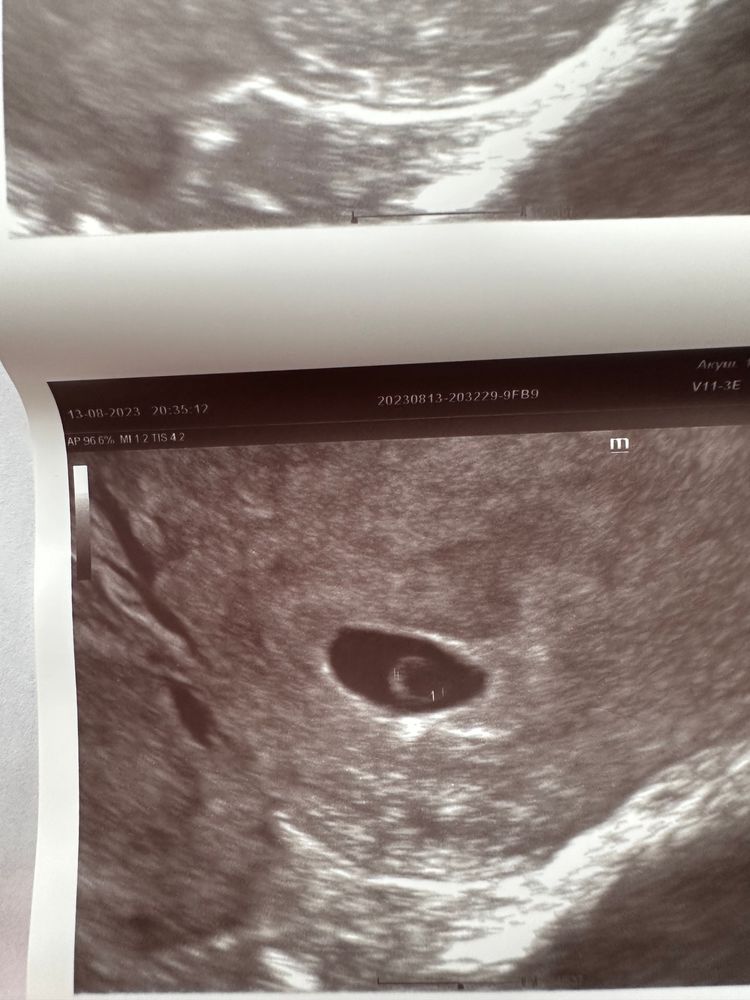

Ната Ли, плодное яйцо есть , пока пустое . Срок сейчас 6 недель и 1 день

Екатерина, Изображение Сходила на узи , появился ЖМ и кажется увидели эмбриончик . Сказали что ждем неделю еще )